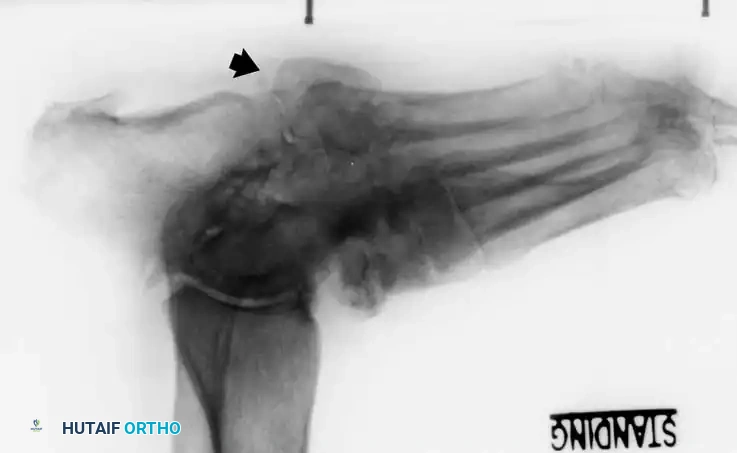

• Stage I (Developmental/Fragmentation): Persistent clinical inflammation. Radiographs reveal osseous destruction, periarticular fragmentation, joint subluxation, or frank dislocation.

* Type 1 (Midfoot): Involves the tarsometatarsal (Lisfranc) and naviculocuneiform joints. This is the most common pattern, affecting approximately 60% of patients. It frequently results in a rocker-bottom deformity.

Lateral subluxation of the forefoot on the midfoot is the most common presentation of Type 1 Charcot. This produces an abducted forefoot, secondary hindfoot valgus, and a contracted Achilles tendon. Surgical correction involves a medial utility incision, resection of the destroyed TMT joints, realignment of the medial column, and rigid fixation using robust hardware (beaming screws, locking plates) or circular external fixation.